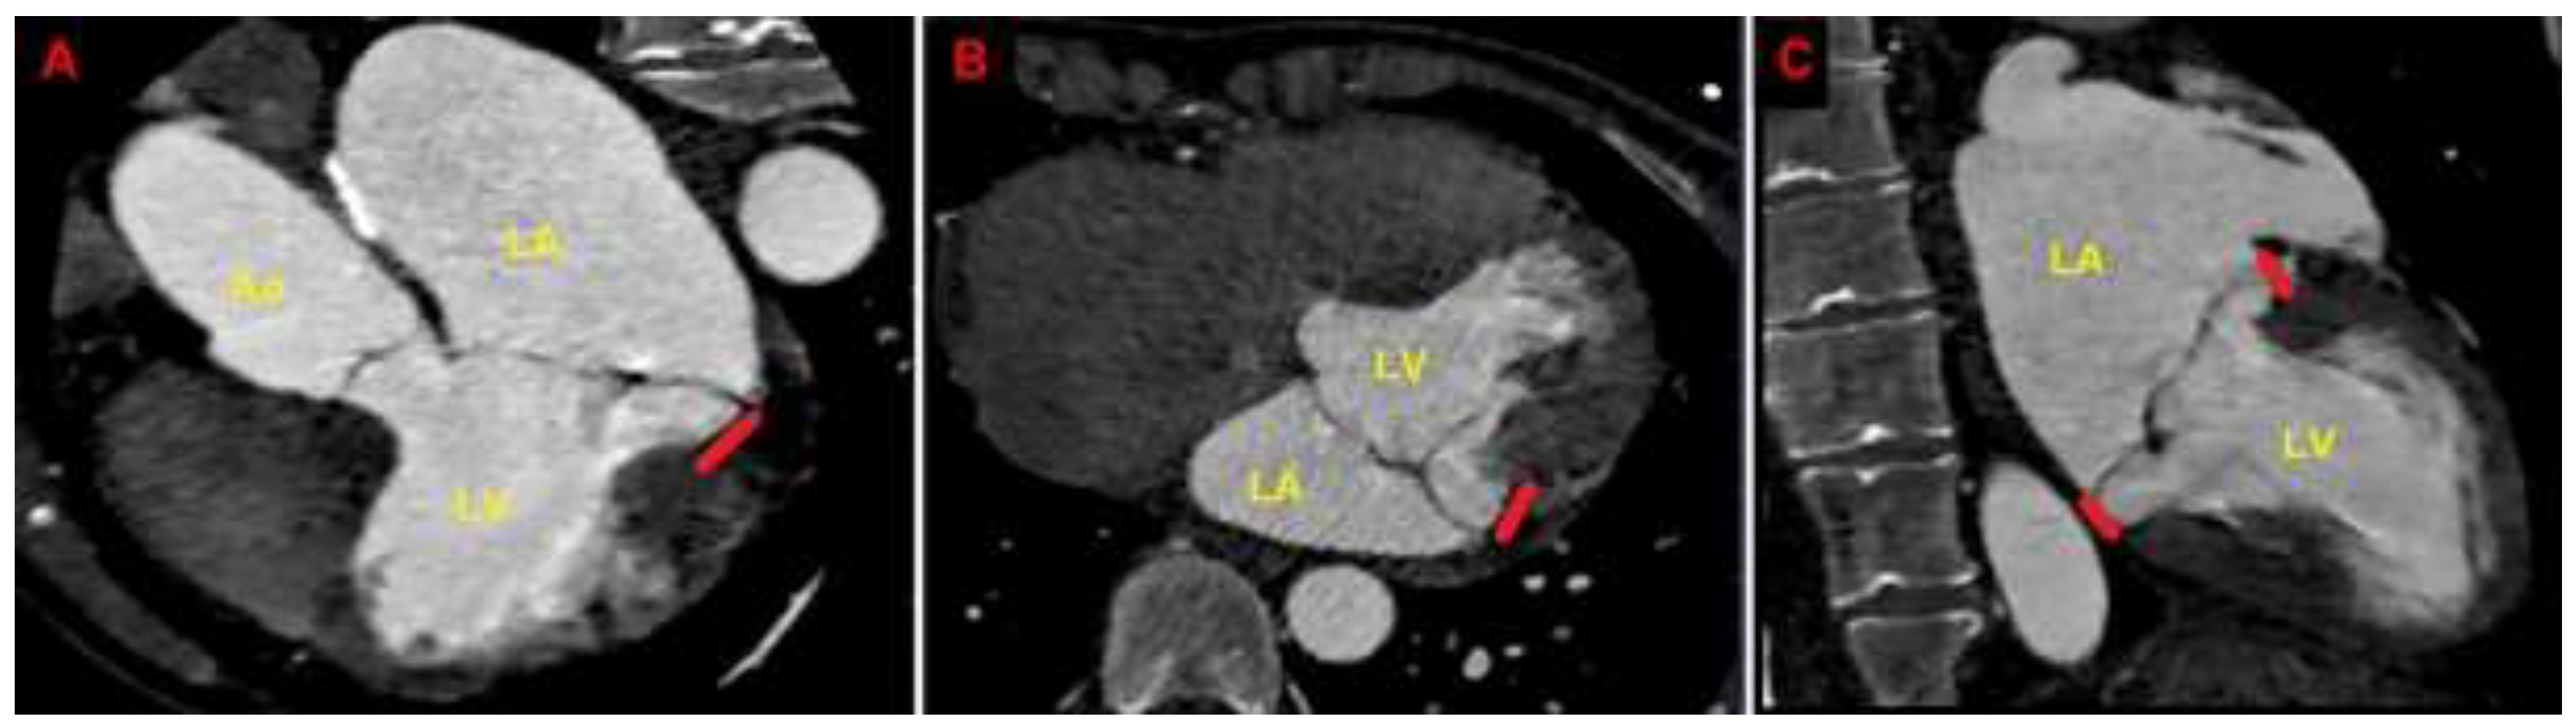

Due to the echocardiographic detection of wide MAD distance and MV floppy degeneration with moderate MR, the patient underwent a diagnostic study comprehensive of TEE, CMR and CCTA. Transesophageal examination (Figure 4), CMR (Figure 5) and CCTA (Figure 6) confirmed the bileaflet floppy MVP, the circumferential extension of MAD and the moderate degree of MR. All the imaging techniques were concordant on the MAD presence and its extent.

CMR excluded areas of focal late gadolinium enhancement (LGE). CCTA showed normal coronary arteries.

Figure 6. Cardiac computed tomography angiography. MAD assessment at end-systole from the multiplanar reconstructed three-chamber view (A), four-chamber view (B) and two-chamber view (C). The bold red line indicates the MAD distance. Ao, aorta; LA; left atrium; LV, left ventricle; MAD, mitral annular disjunction. (A) is reproduced from the paper 10.3390/jcm14051423.